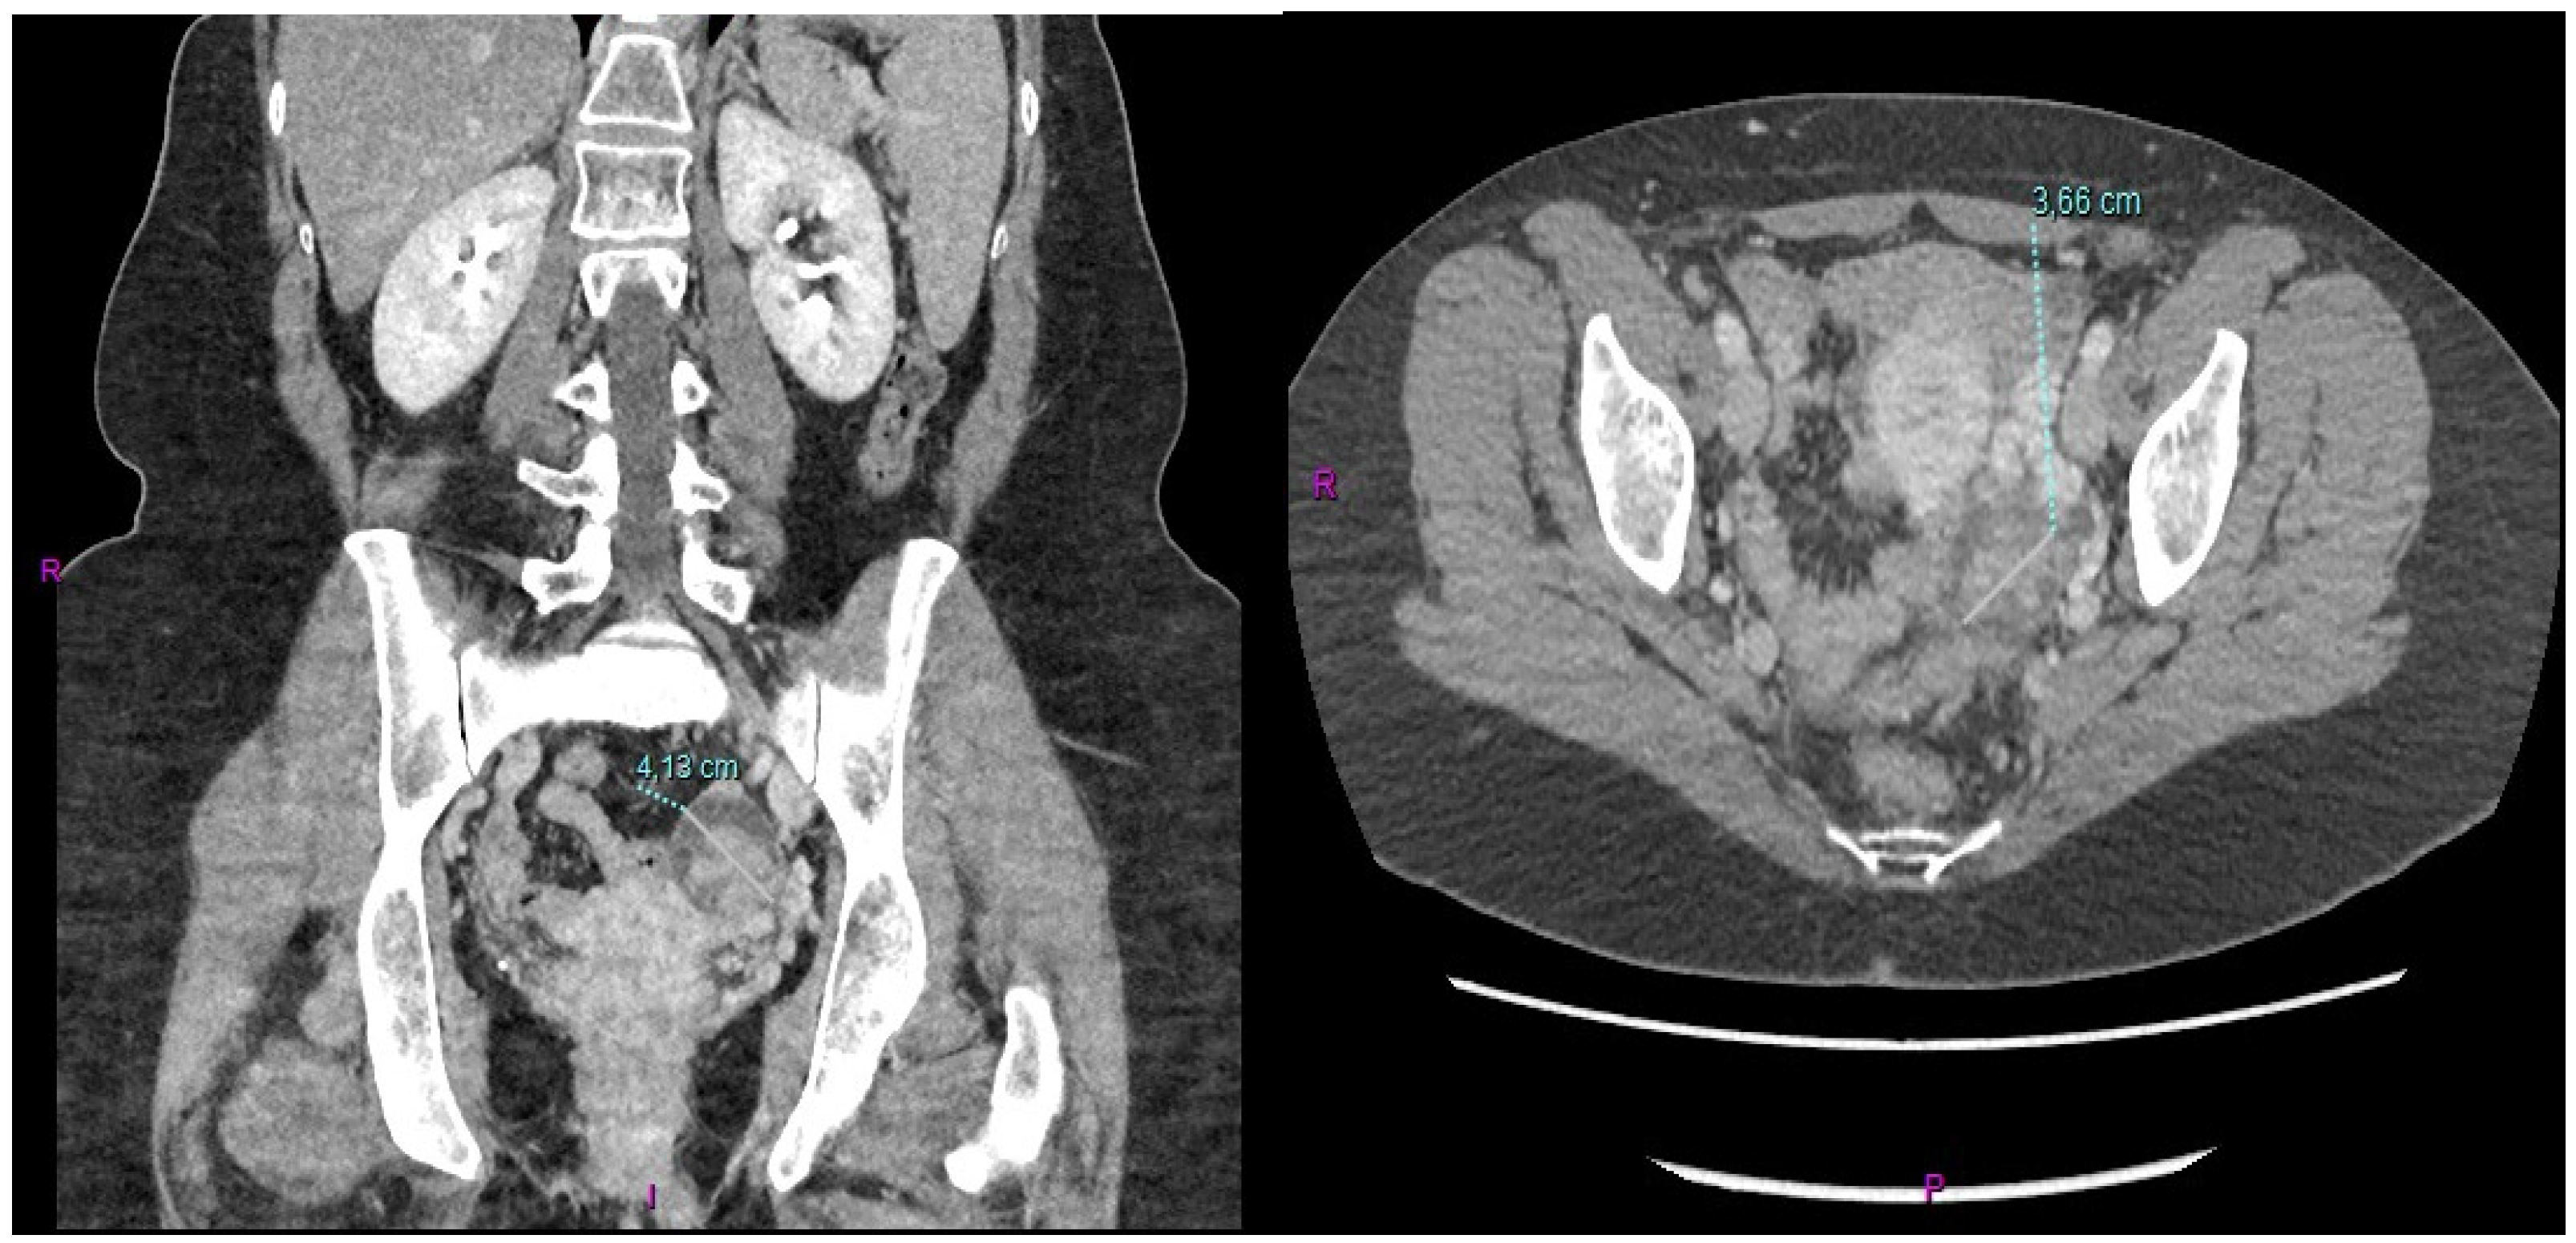

After conjunct oncological and RT assessment, the patient received adjuvant combined CT-RT treatment for a total of 6 months (four cycles of adjuvant capecitabine before and after adjuvant RT with capecitabine as a sensitizer). The CT scan performed a month after the end of adjuvant treatment showed the presence of a 3.6 cm left ovarian mass in the absence of other signs of local or distant relapse of the previous GBC (Figure 1).

Figure 1.

Metastatic involvement of the left ovary derived from the previous GBC.